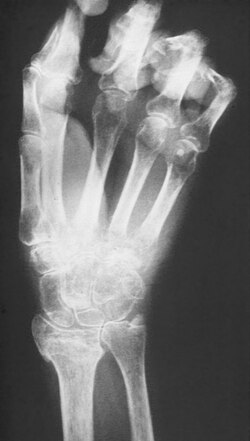

Veränderungen im Röntgenbild

Beim Übergang in das chronische Stadium einige Monate nach Beginn der Erkrankung sind im Röntgenbild meist fleckige Aufhellungen zu erkennen, die durch eine Verringerung des Kalksalzgehaltes im Knochen bedingt sind, wodurch dieser durchlässiger für Röntgenstrahlung wird. Die Entkalkung der Knochen nimmt mit fortschreitender Chronifizierung zu, bis das Bild einer hochgradigen Inaktivitätsosteoporose vorliegt.

Röntgenbild

Im Röntgenbild zeigen sich klassischerweise gelenknahe fleckförmige Entkalkungen. Diese treten jedoch frühestens zwei Monate nach Erkrankungsbeginn auf und können auch völlig fehlen. In späteren Stadien sind die Veränderungen nicht sicher von anderen Knochenatrophien unterscheidbar. Daher spielt das Röntgenbild nur eine untergeordnete Rolle in der Diagnostik.

| Sudeck-Dystrophie der rechten Hand nach schlecht verheilter distaler Radiusfraktur | eigenes Archiv (Orthopädische Universitätsklinik Kiel) | Mehlauge | Datei:Hand-Sudeck.JPG | |